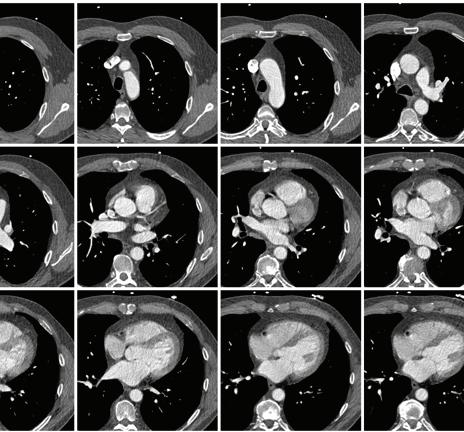

Coronary calcium scoring is a simple, fast and safe imaging exam that uses computerized tomography (CT) to produce pictures of your coronary

arteries and potentially predict heart disease before you experience symptoms. The test is often not covered by private insurance carriers or Medicare, but with a prescription from your doctor, you can receive this valuable test for only $49 at Monmouth Medical Center Southern Campus (MMCSC) and numerous other RWJBarnabas Health locations.

Images provided by coronary calcium scoring help determine if coronary arteries that supply your heart with oxygen-rich blood contain calcium deposits or plaques. These deposits often result from a buildup of fat or other substances and may indicate the presence of atherosclerosis, also called coronary artery disease. Left undetected, plaque buildups can narrow artery walls, leading to chest pain and even a heart attack.

To learn more or to find out if you’re a candidate for coronary calcium scoring due to risk factors such as high blood pressure and/or cholesterol, smoking, stress, a family history of heart disease, lack of physical activity, excess weight or obesity, or advancing age, call 866.675.3226